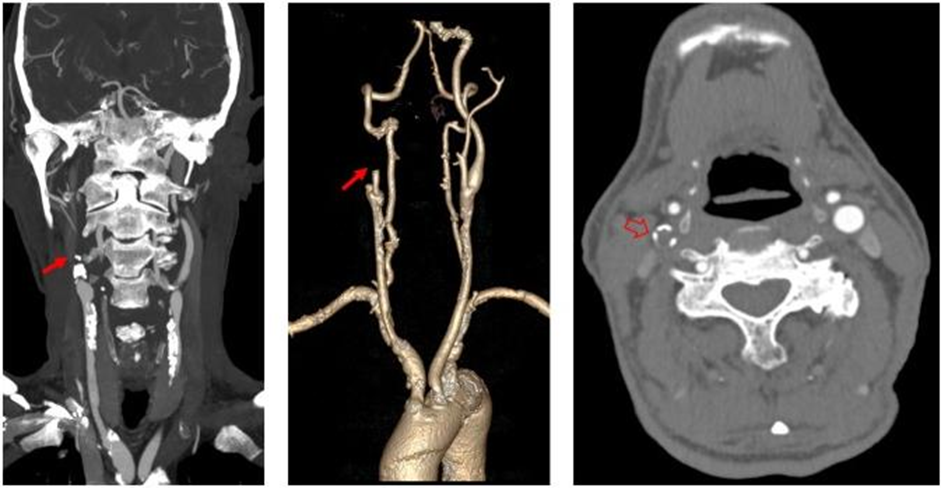

右侧颈内动脉起始部闭塞:三维图像颈内动脉未见显影,横断图像颈内动脉管腔内未见到高密度造影剂充盈。

左侧颈内动脉起始部混合密度斑块,管腔中度狭窄(红箭);右侧颈内动脉起始部钙化密度斑块,管腔轻微变窄(空心箭)。